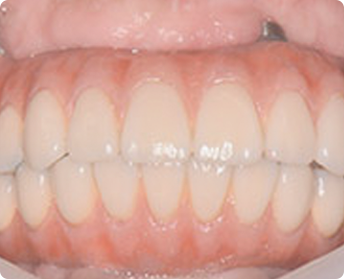

牙齿种植案例展示 TAIKANG BYBO DENTAL